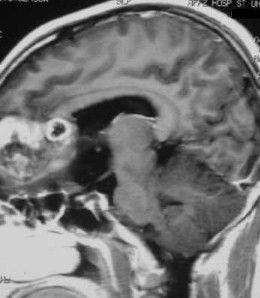

檢查

神經影像學檢查,如CT平掃等。

診斷

結合臨床表現,診斷有賴於神經影像學檢查。